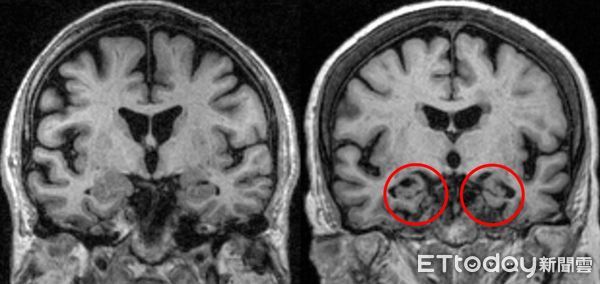

一名50歲謝先生曾是同事眼中效率高、表現卓越的高階主管,但三年前,謝男開始出現嚴重的記憶障礙,不僅經常忘東忘西、無法處理交辦事項,甚至連組織語句、順暢表達都變得困難,最終不得不離職,最後在家人的陪同下就診,確診為「早發型阿茲海默症」。

光田綜合醫院神經內科醫師陳廷斌表示,謝先生沒有任何家族病史,也無三高或慢性疾病,卻在壯年罹病,為家庭帶來巨大衝擊,也打破了許多人認為失智症只與遺傳或老化有關的迷思。

針對輕度阿茲海默症的新療法已有重大突破,陳廷斌指出,近期獲核准的2款藥物是目前唯一被證實能清除阿茲海默症核心毒素「類澱粉蛋白(Aβ)」,進而延緩大腦功能退化的藥物,現光田綜合醫院也已規劃導入,為早期患者提供治療新選擇。